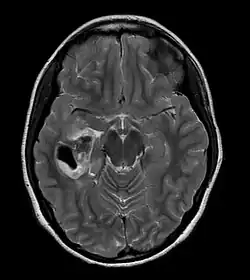

Pleomorphic xanthoastrocytoma

Pleomorphic xanthoastrocytoma (PXA) is a brain tumor that occurs most frequently in children and teenagers. At Boston Children's Hospital, the average age at diagnosis is 12 years.[1]

Pleomorphic xanthoastrocytoma usually develops within the supratentorial region (the area of the brain located above the tentorium cerebelli). It is generally located superficially (in the uppermost sections) in the cerebral hemispheres and involves the leptomeninges. It rarely arises from the spinal cord.

- A CT scan of the brain, and/or an MRI scan of the brain and spine, will be performed. A special dye may be injected into a vein before these scans to provide contrast and make tumors easier to see.